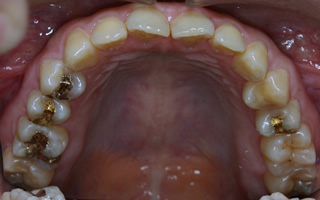

空隙歯列(すきっ歯)の矯正症例

下顎前歯のスペース閉鎖、上顎右側大臼歯の遠心移動による非抜歯での治療

マウスピース型カスタムメイド矯正装置(インビザライン)単独による治療

治療前